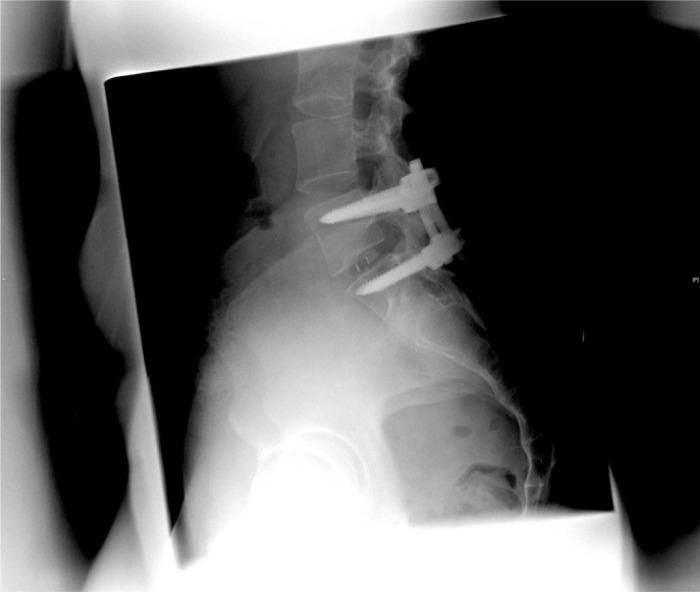

功能性麻醉椎间盘造影:一种新型诊断技术的描述及3例报告。

The functional anaesthetic discogram: description of a novel diagnostic technique and report of 3 cases.

PURPOSE

A new diagnostic technique is described for the evaluation of patients with presumptive discogenic low back pain; the cases of 3 patients in whom the technique was used are presented.

A technique is described in which an anaesthetic catheter is placed into putative symptomatic lumbar discs, the patient elicits his or her typical pain via a position or activity, and anaesthetic or placebo is delivered to the disc. The effect of the injected substance on the patient's pain is then noted.

In one patient, the new test was confirmatory of the results of the provocative discogram; in two patients, the test results were divergent.